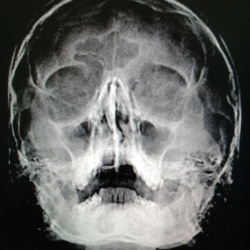

Мужчина 1973 г.р,направлен лором на рентгенографию пазух носа,что за тень в гайморовой пазухе справа,киста?